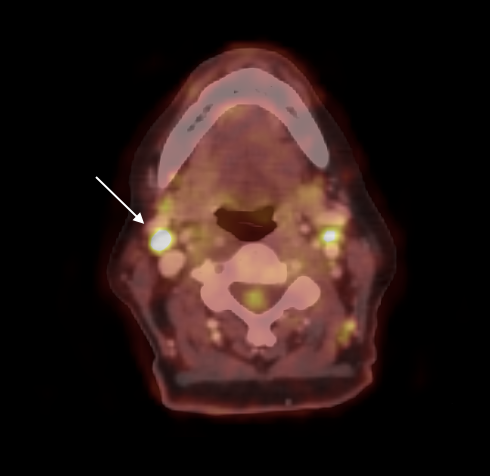

XEOS Aura 10 PET-CT | Case 13: Angioblastic T-cell Lymphoma – Biopsy

(linkki artikkeliin tekstin jälkeen) XEOS AURA 10 PET-CT leikkaussaliin Kliininen tutkimus: Angioblastic T-cell Lymphoma – Biopsy PET-CT-tutkimukset ovat osoittautuneet korvaamattomiksi syöpien diagnosoinnissa ja seurannassa, koska ne tarjoavat vertaansa vailla olevan herkkyyden pahanlaatuisten solumuutosten ja marginaalien havaitsemiseen ja paikallistamiseen. AURA 10 on ensimmäinen leikkaussaliin skaalattu PET-CT, joka tuo PET-CT:n hyödyt ja tutkimukset keskelle leikkaussalia, osaksi kirurgisen…